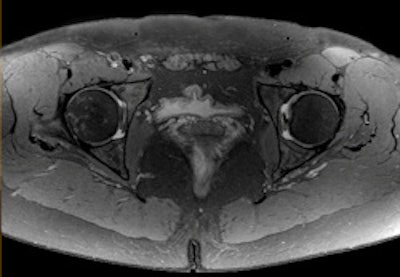

High-resolution MR image of the hip with spectral attenuated inversion-recovery (SPAIR) fat suppression. Image courtesy of Philips.